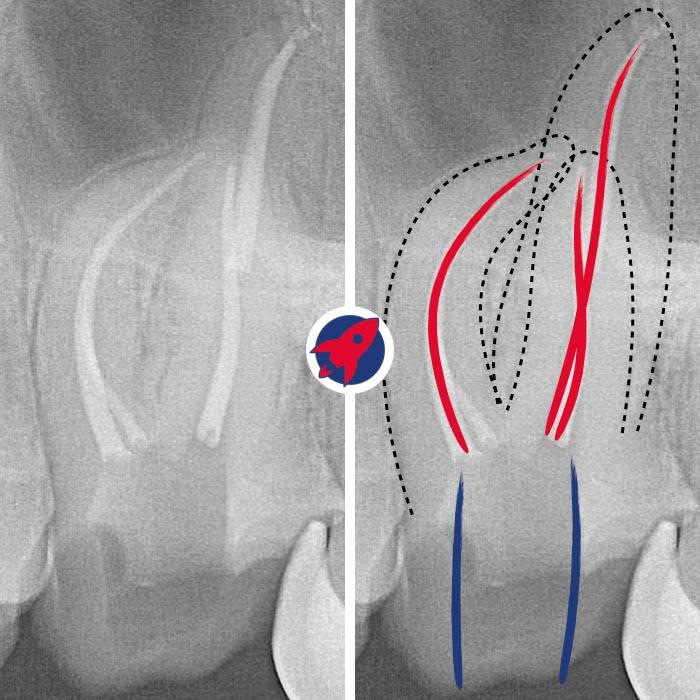

Preserve before replacing.

Rotary instrumentation, chemical disinfection, and microscopy with a clear plan for definitive restoration.